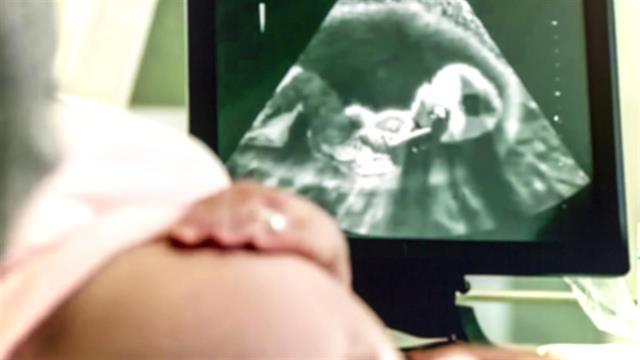

Τα καρδιολογικά προβλήματα των εμβρύων ποικίλλουν από ήπια έως πολύ σοβαρά. Κάποια χρειάζονται χειρουργική θεραπεία στη νεογνική περίοδο, ενώ άλλα μπορεί να υποστρέψουν αυτόματα με τη πάροδο του χρόνου. Ο παιδο-εμβρυοκαρδιολόγος θα σας συμβουλεύσει για τη σοβαρότητα του καρδιολογικού προβλήματος του εμβρύου, αφού πραγματοποιήσει έναν εξειδικευμένο υπέρηχο, το εμβρυϊκό υπερηχοκαρδιο-γράφημα.

Η εμβρυϊκή υπερηχοκαρδιογραφία ανιχνεύει καρδιακά προβλήματα πριν τη γέννηση του εμβρύου, επιτρέποντας έτσι την άμεση καρδιολογική ή καρδιοχειρουργική αντιμετώπιση, πριν το νεογνό επιβαρυνθεί αιμοδυναμικά. Έτσι επιτυγχάνεται η καλύτερη επιβίωση και το καλύτερο δυνατό μακροχρόνιο αποτέλεσμα. Ο εμβρυο- καρδιολόγος θα σας συμβουλεύσει για τη σοβαρότητα του καρδιολογικού προβλήματος και θα σας εξηγήσει αναλυτικά τι να περιμένετε.

Με λίγα λόγια η εξέταση της καρδιάς του εμβρύου από ειδικό εμβρυοκαρδιολόγο με το εμβρυϊκό υπερηχοκαρδιογράφημα είναι μια απλή και ασφαλής μέθοδος που οδηγεί στην ανίχνευση ή τον αποκλεισμό ηπίων έως και πολύ σοβαρών καρδιολογικών προβλημάτων. Η έγκαιρη διάγνωση και η σωστή θεραπεία και συμβουλευτική οδηγεί στο καλύτερο δυνατό αποτέλεσμα για το έμβρυο και την οικογένειά του.